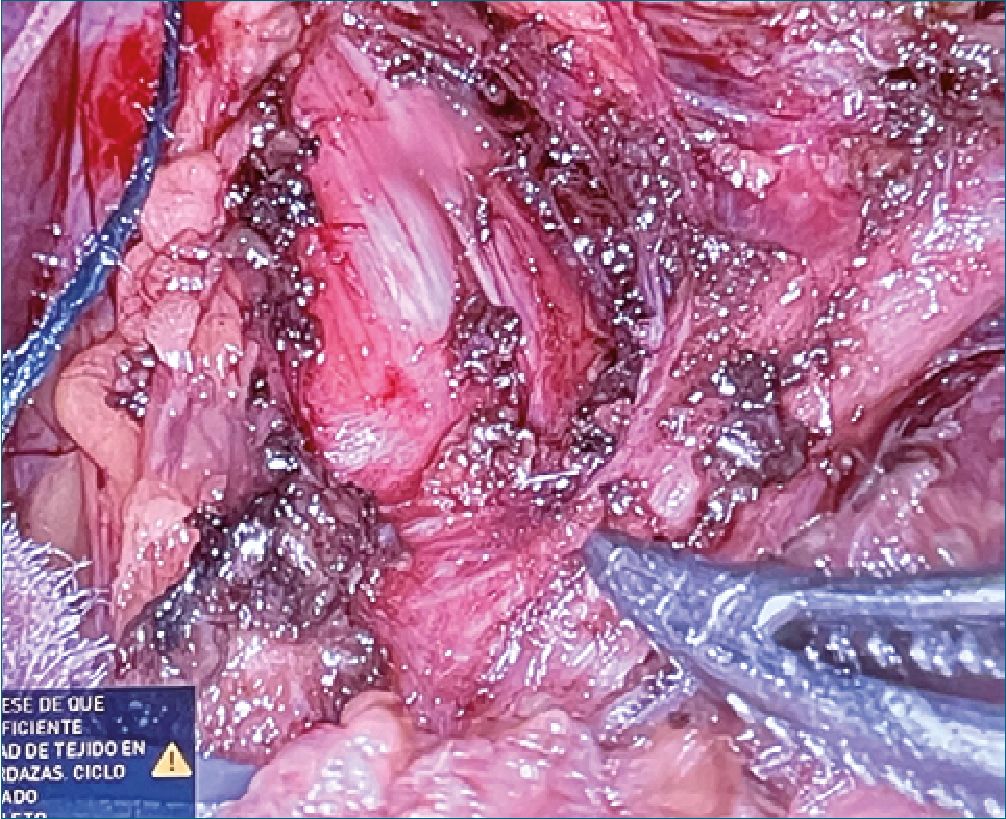

Figura 1. Fotografía obtenida durante la liberación robótica del ligamento. En ella se puede ver la compresión ejercida sobre la arteria celíaca y sus estructuras adyacentes.

Se realizó una ecografía intraoperatoria antes de la liberación robótica del ligamento que mostró un flujo a gran velocidad en la arteria celíaca, sugestivo de compresión. Posteriormente, se realizó la liberación del ligamento, que condicionaba una estenosis de la arteria celíaca inmediatamente proximal a la salida de la arteria gástrica izquierda, como puede apreciarse en la Figura 1. Tras ello, se repitió la ecografía intraoperatoria, que evidenció una reducción considerable de la velocidad del flujo y una mejoría significativa de la estenosis.